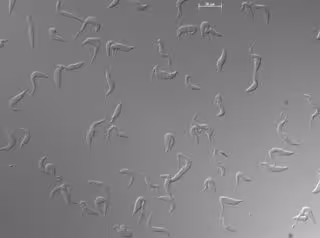

Células de Trypanosoma brucei en cultivo observadas al microscopio. /

Células de Trypanosoma brucei en cultivo observadas al microscopio. / - IPBLN-CSIC